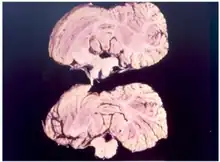

Kuru is a rare, incurable, and fatal neurodegenerative disorder that was formerly common among the Fore people of Papua New Guinea. Kuru is a form of transmissible spongiform encephalopathy (TSE) caused by the transmission of abnormally folded proteins (prions), which leads to symptoms such as tremors and loss of coordination from neurodegeneration.

Kuru, a transmissible spongiform encephalopathy, is a disease of the nervous system that causes physiological and neurological effects which ultimately lead to death. It is characterized by progressive cerebellar ataxia, or loss of coordination and control over muscle movements.[11][12]

Kuru is diagnosed by reviewing the patient's history of cerebellar signs and symptoms, performing neurological exams, and excluding other neurological diseases during exams.[15] The symptoms evaluated are typically coordination issues and involuntary muscle movements, but these markers can be confused with other diseases that affect the nervous and muscle system; physical scans are often required to differentiate Kuru from other disorders.[26][27] There is no laboratory test to determine the presence of Kuru, except for postmortem evaluation of central nervous system (CNS) tissues, so diagnoses are achieved by eliminating other possible disorders.